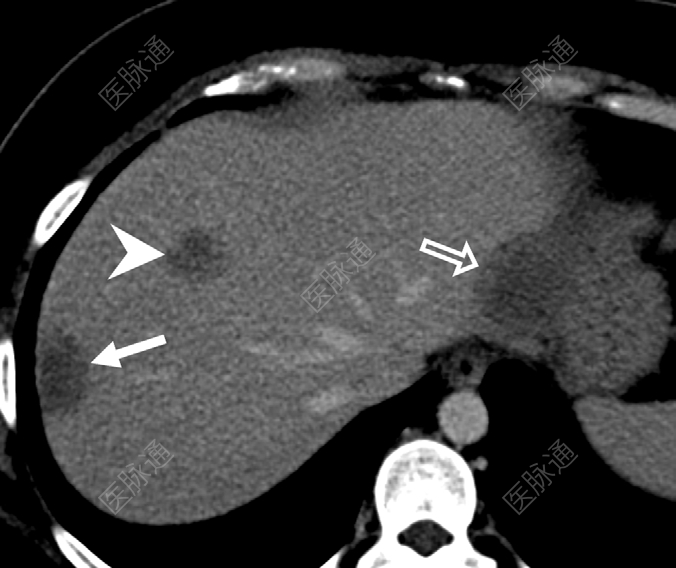

图1:上腹部斜轴位CT:第7段肝包膜下病灶(实箭)、第2段肝包膜下病灶(空心箭)及第8段非肝包膜下病灶(箭头)。